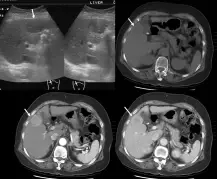

圖片呈現 2×2 四格影像:

- 左上圖(超音波):肝臟超音波,白色箭頭指向一個邊界尚清楚的低迴音病灶,位於肝臟右葉的前下方區域,近膽囊窩(gallbladder fossa)旁。

- 右上圖(pre-contrast CT):平掃期,可見肝臟右葉前下方(近膽囊旁)有一約 2–3 cm 低密度病灶,箭頭標示其位置。病灶位於中肝靜脈(middle hepatic vein)與右肝靜脈(right hepatic vein)之間,且位於門靜脈分叉平面以下(infraportal)。

- 左下圖(arterial phase CT):動脈期,病灶呈明顯高增強(arterial enhancement / hypervascularity),典型「快進」表現,符合肝細胞癌(hepatocellular carcinoma, HCC)的血管特性。

- 右下圖(venous phase CT):門靜脈期,病灶密度相對下降,呈現「快出」(washout)現象